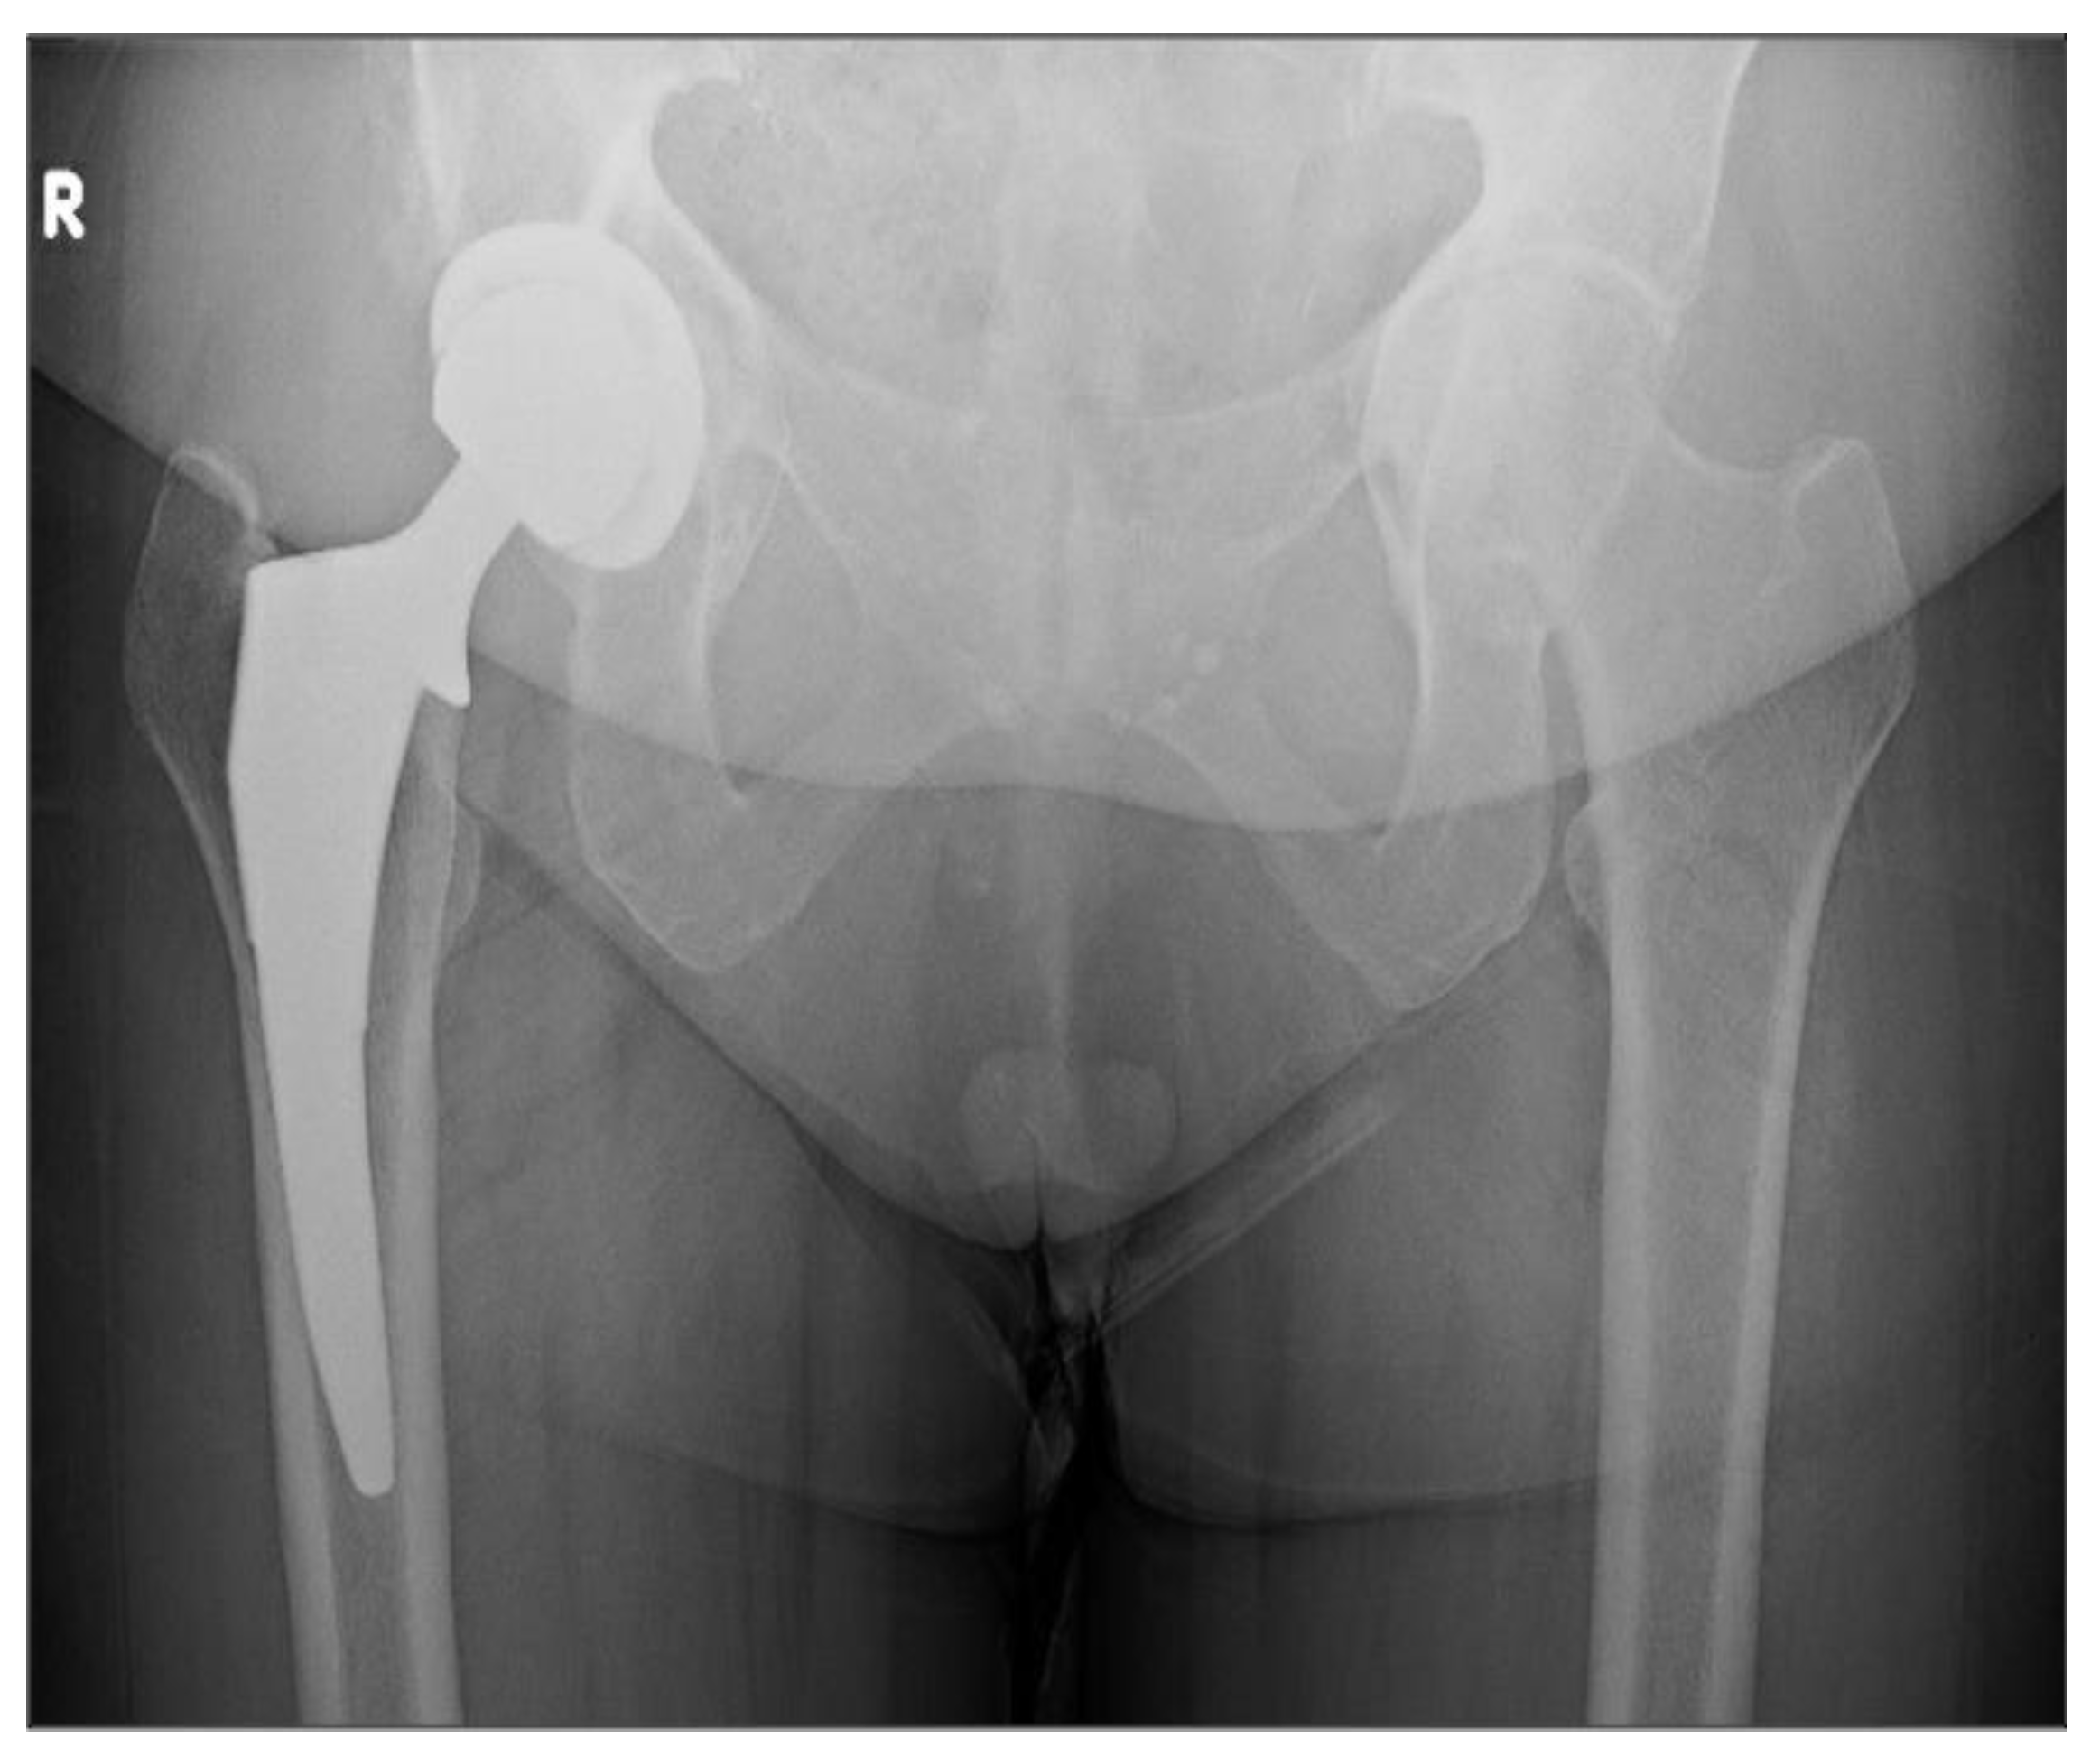

| Class | Ilioischial Line | Iliopectineal Line | Recommended Treatment |

|---|---|---|---|

| I | Intact (femoral head medialized) | Intact | Implant Placement: Lateralization of acetabular component to match native rim. Standard component needed, no need for screw augmentation. Bone graft: Not likely required. |

| II | Violated | Intact | Implant Placement: Lateralization of acetabular component to rim, consider use of larger or jumbo component. Screw fixation optional. Consider lateralized acetabular liner. Bone Graft: Likely required medially with impaction grafting. |

| III | Violated | Violated | Implant Placement: Lateralization of acetabular component, consider use of jumbo, deep profile, revision, or multi-hole component. Screw fixation is strongly recommended in multiple planes to augment construct stability. Consider lateralized acetabular liner. Bone Graft: Universally required. Autograft reamings and morselized cortical bone from native head is recommended, consider use of additional allograft bone to fill large defects. Powdered antibiotic can be added to graft mixture to reduce risk of prosthetic joint infection. |